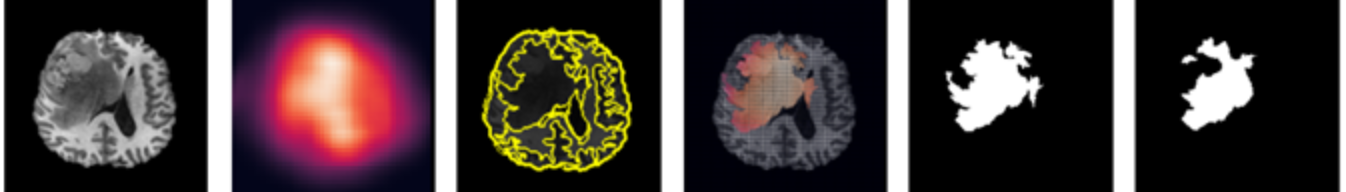

To automate the segmentation process, we apply superpixel segmentation on the query slice and select the segment with the most reconstruction loss, based on the constructed heatmap. Superpixel based techniques segment an image into a collection of connected pixels which are similar in colour and texture. This allows us to capture common features in our slice and locate features our inpainting network failed to reconstruct. Although there exists many algorithms that perform superpixel segmentation, we choose to implement Felzenszwalb’s efficient graph-based segmentation [13] as it segments tumours more accurately than other methods.

Segmentation Quality. As shown in table 1, the proposed system outperforms AnoGAN [2]. A window of size 32 indicates the highest accuracy and consistency in handling various sized tumours, with a mean Dice score of 0.771 and of standard deviation 0.176. Other window sizes express high variability, performing well either on small or large sized tumours. The effect of using superpixel results in higher definition segmentations, allowing the capture of regular and more abstract tumours, which would not be possible with manual thresholding. Additionally, for evaluation, we trained a single network to reconstruct all values of (8, 16, 32 and 64). We obtained good reconstruction results, but this resulted in partial reconstructions of tumorous regions during the sliding window process, indicating a single optimal network for all tumour sizes is not possible with our method.

In Felzenszwalb’s algorithm [13], the scale parameter influences the segment size. Although a constant scale value of 75 was used in the evaluation process, there were times when a larger or smaller value would have produced better segmentation results. Figure 6 illustrates how a scale value below 100 would result in the inner segment being selected. To prevent this, an appropriate scale value must be manually chosen before the segmentation process.